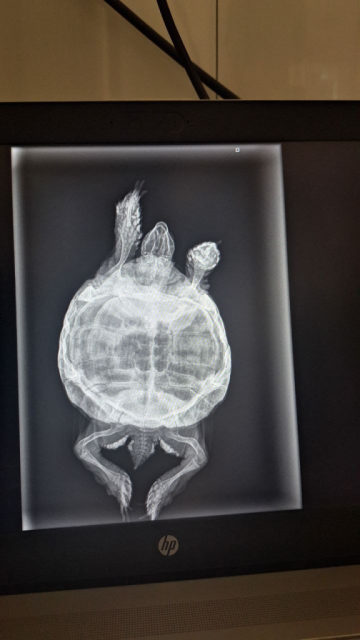

23.04 были на приеме в клинике Лимпопо у Есенова Алана. Был произведен осмотр и сделан рентген. На снимке есть затемнение в легком. Сделали уколы: элеовит, байтрил. Байтрил назначен через день, элеовит повторно через 2 недели.

image.thumb.png.a19ba07254fc97e2ccccad5375c9803f.png

photo_2024-04-25_11-11-45.jpg